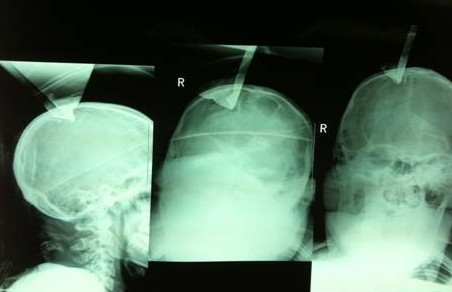

我們先看看這個(gè)患者的片子,從片子上很明顯,鋼板穿過了右頂骨造成開放性骨折。